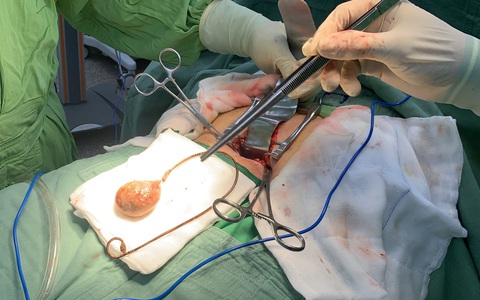

Bệnh viện Đa khoa khu vực Cai Lậy vừa phẫu thuật lấy viên sỏi bàng quang có kích thước "khổng lồ" to như quả trứng gà cho một người đàn ông 62 tuổi quê ở huyện Cái Bè, tỉnh Tiền Giang.